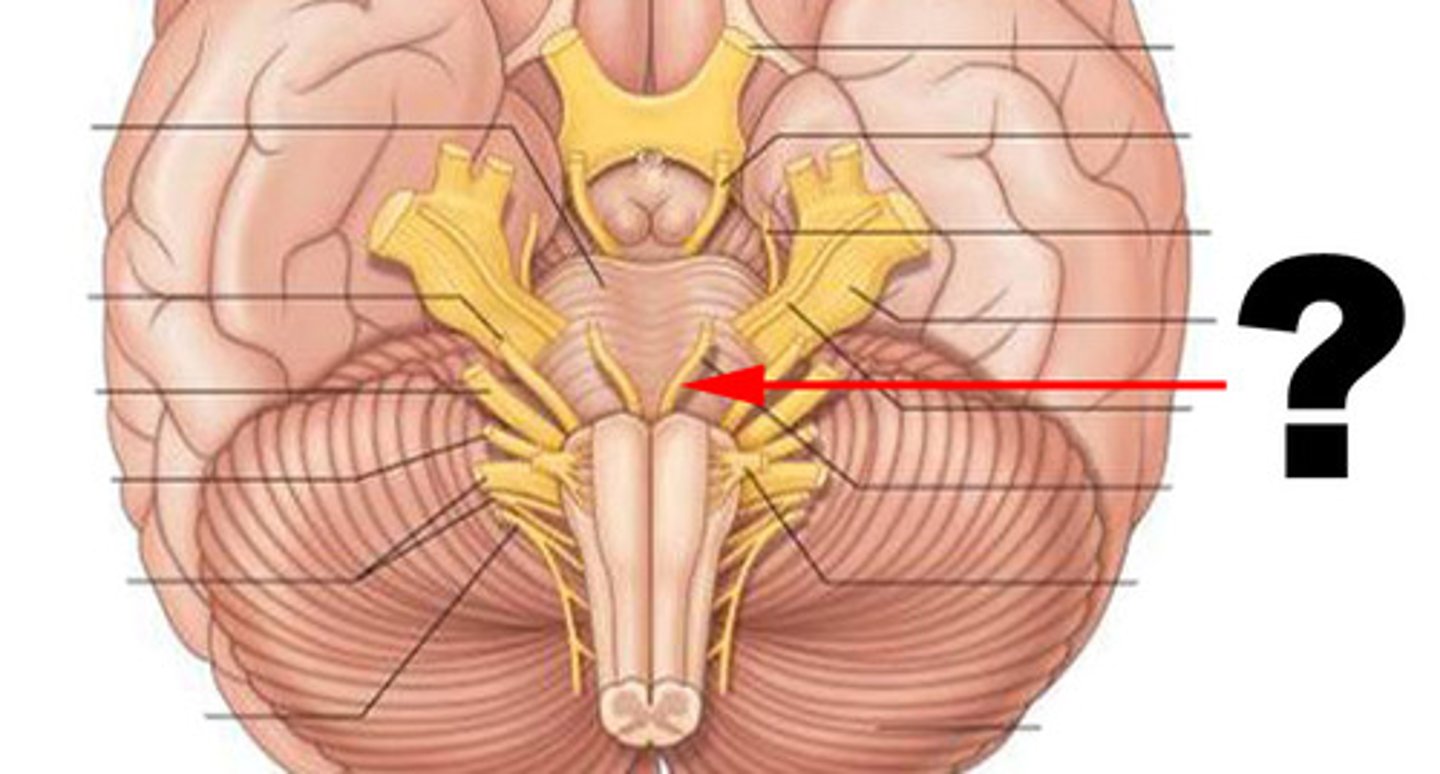

cranial nerves

12 pairs of nerves that carry messages to and from the brain

cerebral peduncles

located on the ventral surface of midbrain. has corticospinal tract (voluntary movements) & corticobulbar tracts (motor control of face & head)